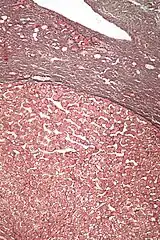

Micrograph of a hepatic adenoma (bottom of image). H&E stain | |

Hepatic adenomas are, typically, well-circumscribed nodules that consist of sheets of hepatocytes with a bubbly vacuolated cytoplasm. The hepatocytes are on a regular reticulin scaffold and less or equal to three cell thick.

The histologic diagnosis of hepatic adenomas can be aided by reticulin staining. In hepatic adenomas, the reticulin scaffold is preserved and hepatocytes do not form layers of four or more hepatocytes, as is seen in hepatocellular carcinoma.

Cells resemble normal hepatocytes and are traversed by blood vessels but lack portal tracts or central veins.

- Micrograph of hepatic adenoma. H&E stain